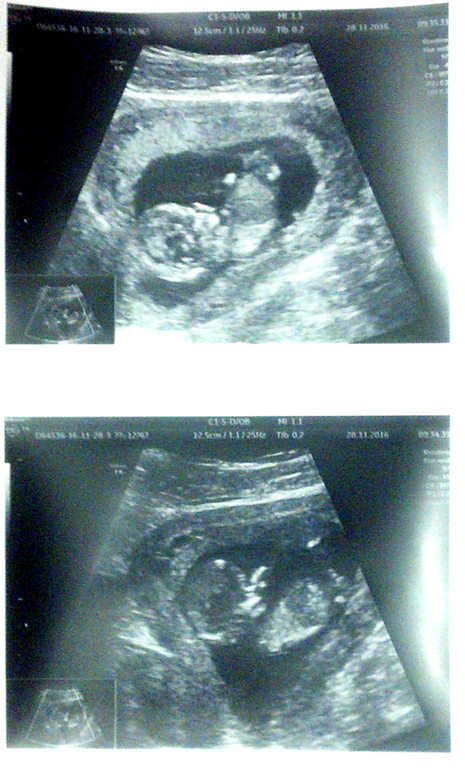

Девушки, утром у меня был первый скрининг! Я наконец-то увидела своего малютку во всей красе. ^_^

Узистка не обнаружила никаких аномалий, развитие идёт как надо. Ростик уже 12,5 см! Ого! На целых 10,5 см вымахал за каких-то 5 недель! Вот это да! Чудеса природы... Но всё соответствует сроку. Только вот не это меня поразило больше всего...

Девушки, он там... Месится! Первое слово, что пришло на ум при виде его кувыркашек :)) Вообще кувыркается как космонавт! Не, я-то думала, что лежит спокойненько, и ручками-ножками болтает. Неа, егозит по-полной)) Это незабываемо) Вот ведь сколько энергии) Я не удивлюсь, если скоро начну ощущать его возню)

Спрашивала про моё предлежание плаценты, мне сказали - нет, плацента сейчас там где надо. :)